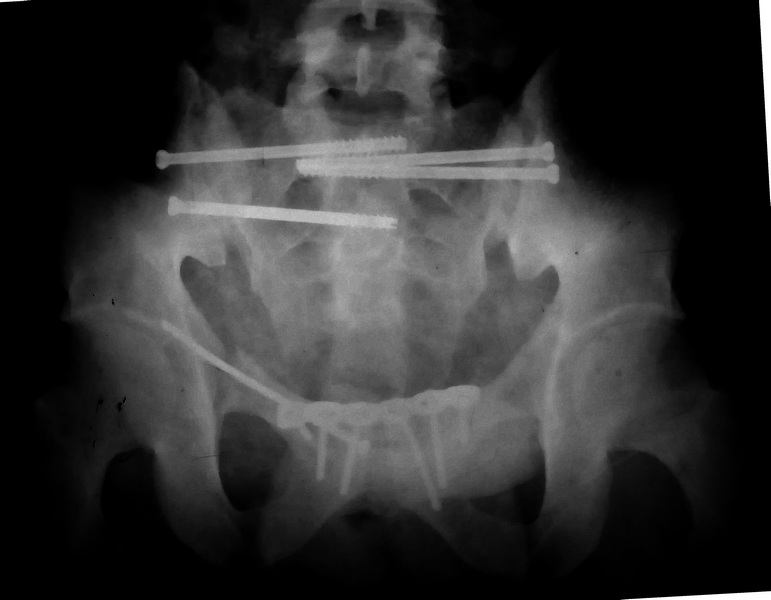

Коллеги, как и когда вы бы разрешили нагрузку в такой ситуации.

Молодой парень, без соматики. Сейчас чуть больше 2-х нед после операции,

швы сняты, мочится сам. Был тяжелый, после операции дней 10 пытался

выполнить лежа поперечный шпагат (успешно, так и лежал большей частью,

может быть из-за обширной гематомы промежности). Репозиция не

идеальная, но фиксация довольно надежная, за 2 нед ничего не

разъехалось". Сейчас пришел в ум. Когда, по-вашему, можно дать нагрузку,

и на какую ногу, или на обе? Или вообще подскажете

программу реабилитации.

PS Заранее извиняюсь за качество снимков, до не делали (body scan),

если не видно - то - полные разрывы КПС с двух сторон. после КТ

сломался. Неврологии вроде бы нет.